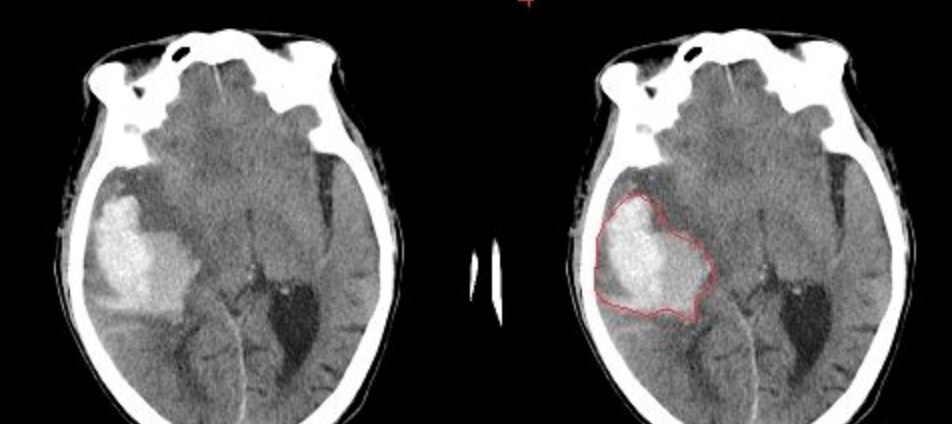

- 脑出血: 在CT影像上,高密度的区域就大概率是一块出血,如下图红色框区域。

- 脑出血: 在CT影像上,高密度的区域就大概率是一块出血,如下图红色框区域。